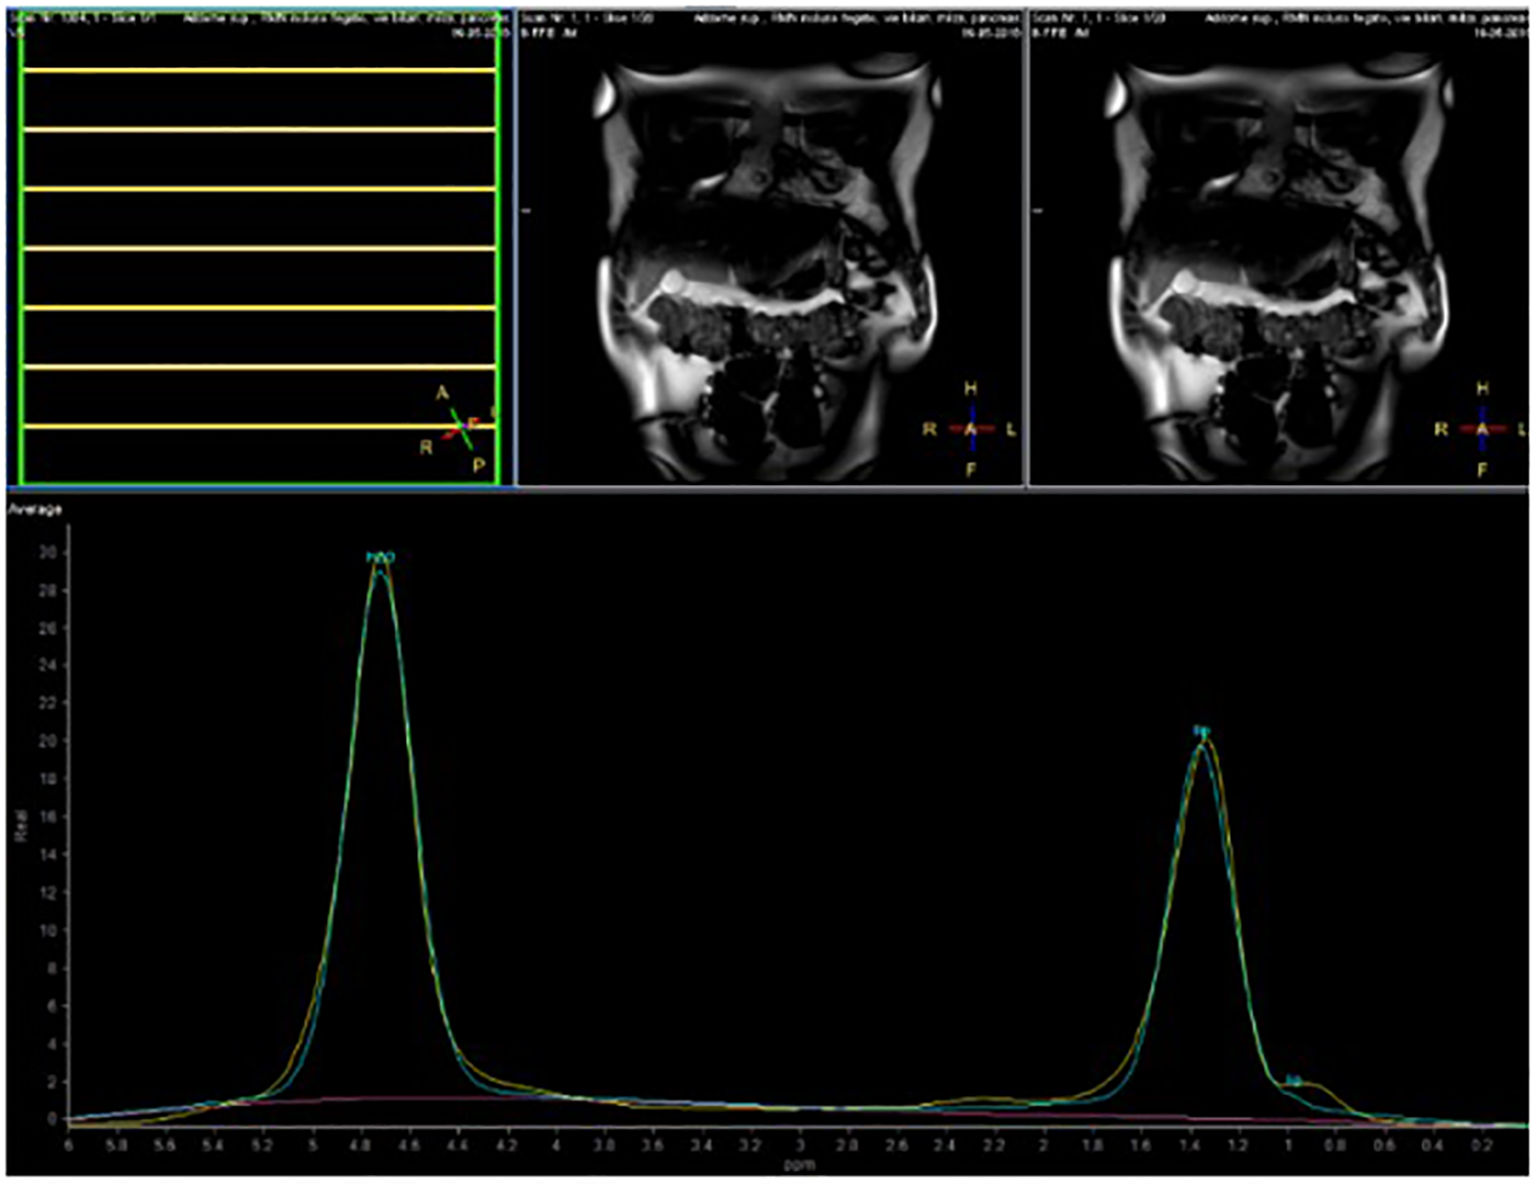

The volunteers subsequently underwent MRI: 28 subjects (23.9%) had no steatosis (steatosis percentage <5%), 64 (54.7%) had mild steatosis (steatosis percentage 6%–33%), and 25 (21.4%) had moderate steatosis (steatosis percentage 34%–66%). No subjects with severe steatosis (>66%) were identified (Table 1). GE T1-weighted in-phase images show loss of hepatic signal on opposed phase images, demonstrating the presence of steatosis (Figures 2A, B). However, a quantification of fat fraction is not possible. On the other hand, both spectroscopy and PDFF sequence allow a reliable evaluation of the liver fat fraction. The PDFF sequence allows to evaluate the whole liver (Figures 3, 4).

Figure 3

Case 32: spectroscopy evaluation.